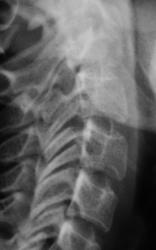

Пациент предъявляет жалобы на боли в плечевом суставе. Направлен на рентгенографию плечевого сустава хирургом. Со стороны плечевого сустава (рентгенограмма) патологических изменений не выявлено. Произведено исследование шейного отдела позвоночника.

Валентин Львович! Не могу посчитать позвонки, перекрываются углом нижней челюсти. Ну то, что имеется остеохондроз, это понятно. Аномалия развития в виде расщепления остистого отростка позвонка или C2 или C3 позвонка. Но откуда у С1 остистый отросток?

Что же касается данной шеи: считаю необходимым дообследования - рентгенография С1 позвонка "через рот", более информативно будет.